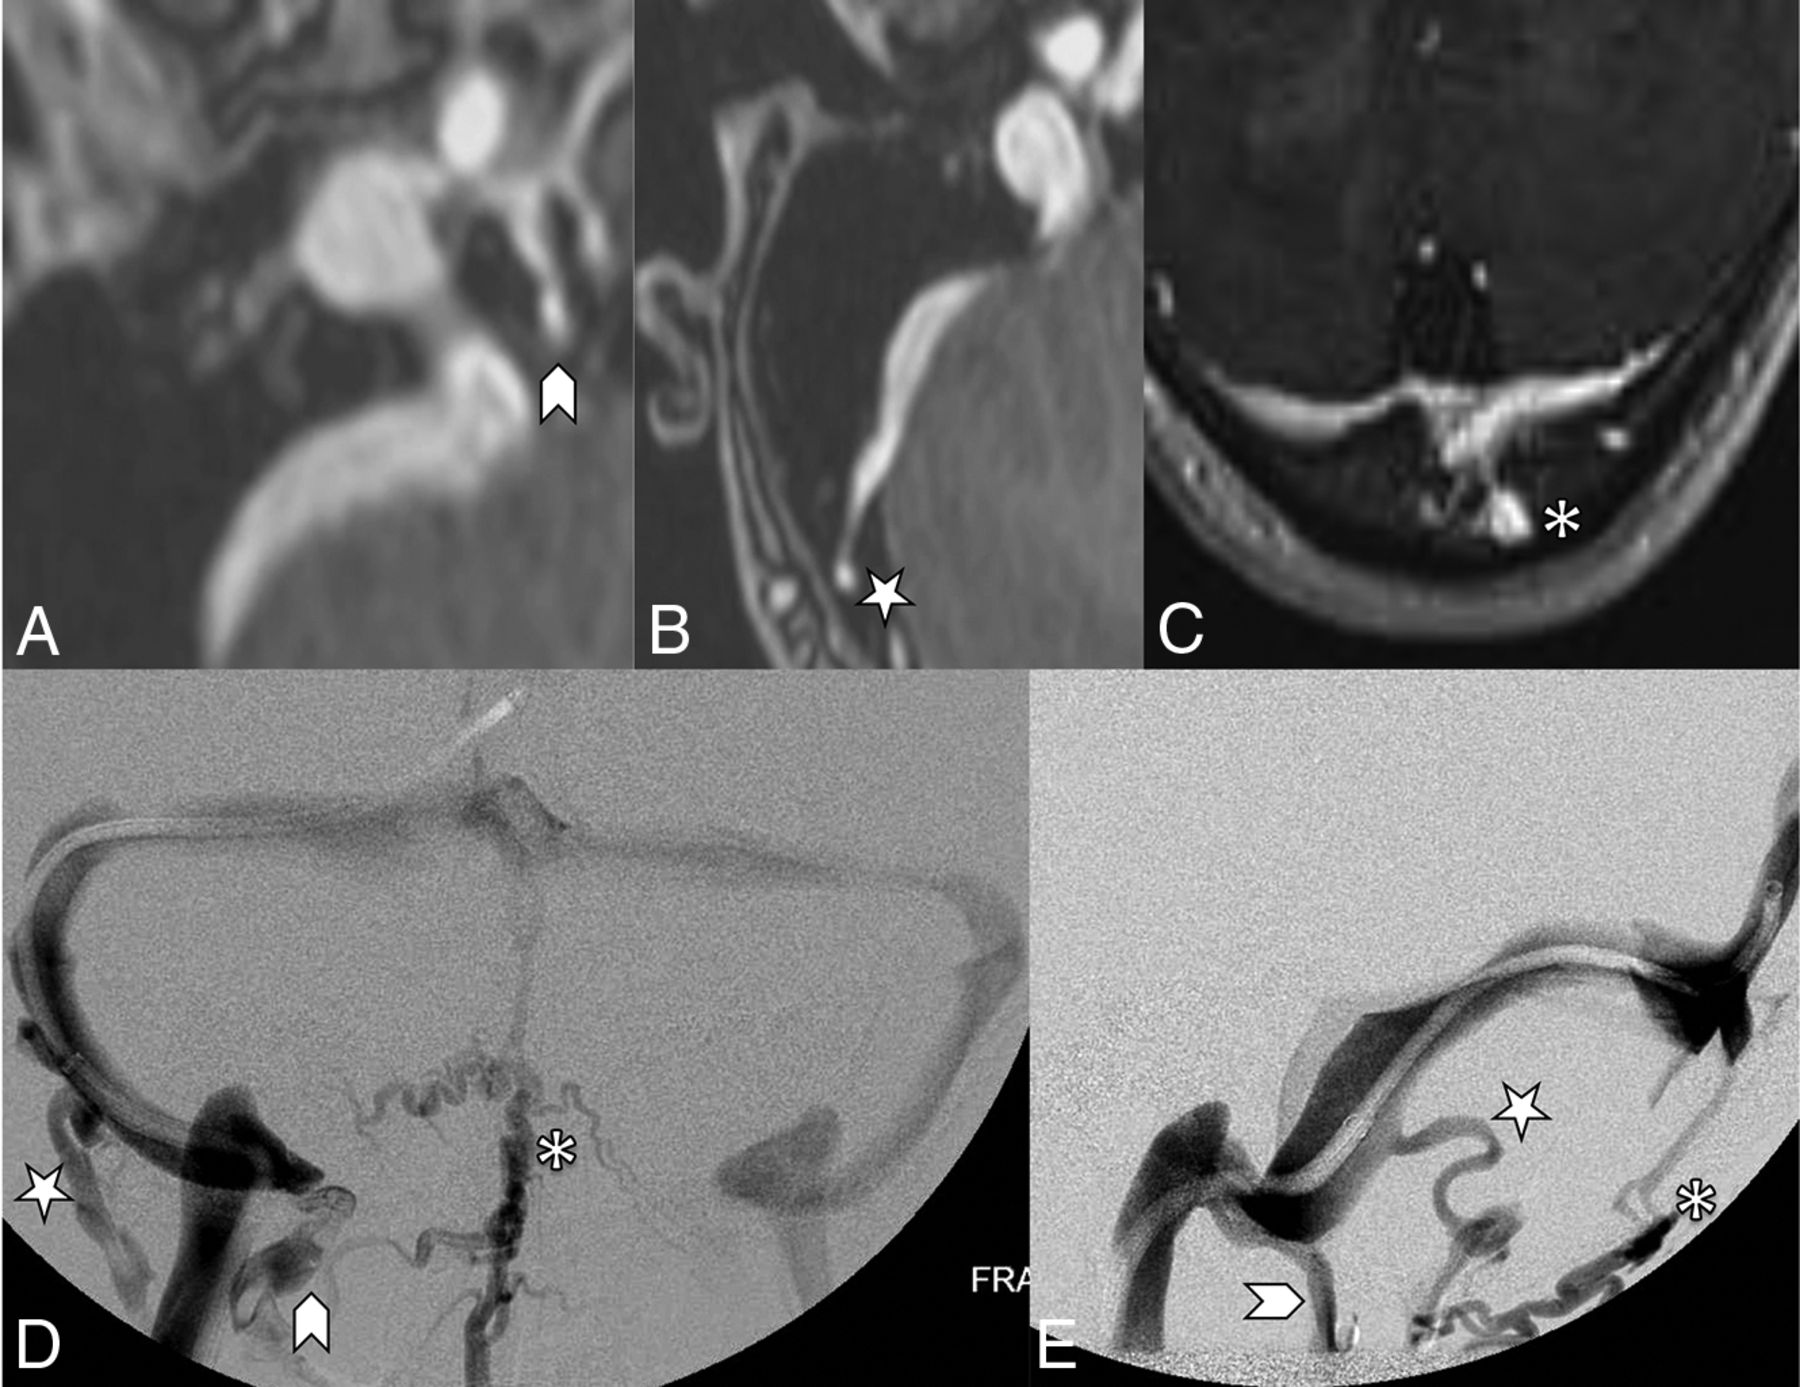

The other recorded imaging findings included the presence or absence of prominent emissary veins, optic nerve tortuosity, cephalocele, sella appearance, sinus enlargement versus aneurysm, and internal jugular bulb diverticula as shown in Fig 3. The presence of prominent emissary veins was initially detected on MRV and corroborated on subsequent conventional venography. The 3 subtypes classified were condylar arising from the internal jugular bulb, mastoid arising from the sigmoid sinus, and occipital arising from the torcula as shown in Fig 4.

Objective parameters implemented in recording corollary findings of both idiopathic intracranial hypertension and pulsatile tinnitus cohorts. A, Marked optic nerve tortuosity, with >50% of optic sheath width deviation noted relative to its expected straight path along the optic canal (white arrows). Bilateral ≥ 5-mm internal jugular bulb diverticula, as seen on MRV (B) and catheter venography (C) images (curved white arrows). D, Cerebellar tonsil projecting 1–3 mm below the foramen magnum, referred to as ectopia (black arrow). E, Empty sella recorded if there is >75% loss of pituitary height (curved black arrow). F, Coronal T2 MR imaging demonstrates a left temporal lobe cephalocele through the tegmen tympani (arrowhead) and CSF in mastoid air cells (star).

Contrast-enhanced MRV images (A, B, and C) highlighting features of the emissary veins categorized in this study. A, A condylar vein is seen arising from the internal jugular vein bulb extending through the condylar canal (arrowhead). B, A mastoid emissary vein is seen arising from the sigmoid sinus traversing the mastoid foramen (star). C, An occipital emissary vein is seen arising from the torcula extending through the calvaria (asterisk). Conventional venography frontal (D) and lateral (E) images showcase the 3 emissary vein types categorized in this study. The condylar vein (arrowhead) extends inferiorly toward the vertebral plexus. The mastoid emissary vein (star) extends posteriorly and inferiorly to join the suboccipital plexus and external jugular vein. The occipital emissary vein (asterisk) drains inferiorly into the suboccipital plexus.

Optic nerve tortuosity was evaluated on axial thin-section T1- and T2-weighted images when available. Tortuosity was classified as marked if the optic sheath width deviated >50% of its diameter relative to its expected straight path from the optic canal and minimal if <50% of its diameter. Cephaloceles were characterized as being either present or absent.

The degree of mass effect on the sella was graded in reference to the noncompressed posterior pituitary gland relative to the expected pituitary gland height in each case. The sella was characterized as empty if >75% of pituitary parenchymal height was lost on sagittal plane imaging and partially empty if anywhere between 25% and 75% loss of pituitary height was identified. The cerebellar tonsils were graded according to location on sagittal plane imaging. ‘Above’ was used when both cerebellar tonsils were above the foramen magnum, noting 4 separate patients with prior Chari 1 surgical intervention were separately categorized. ‘At’ was used when one or both cerebellar tonsils were at the foramen magnum. ‘Ectopia’ was used when one or both cerebellar tonsils were projecting below the foramen magnum by 1–3 mm. Internal jugular bulb diverticula were evaluated on coronal plane MRV imaging, with sizes graded according to height projecting above a line drawn perpendicular to the distal sigmoid sinus insertion into the internal jugular vein. Diverticula were categorized as either being small (<5 mm in height) or prominent (≥5 mm in height).